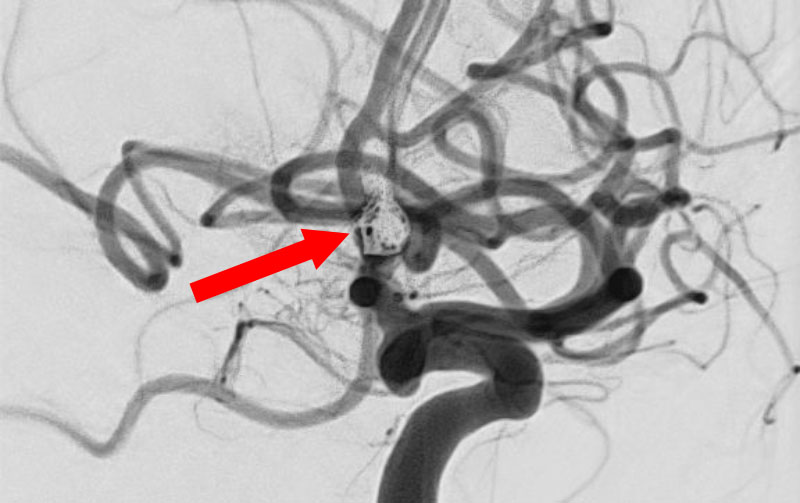

'25年10月

くも膜下出血

前交通動脈瘤破裂

40代

大阪府の病院

No.1589 手術前

No.1589 手術中

No.1589 手術後